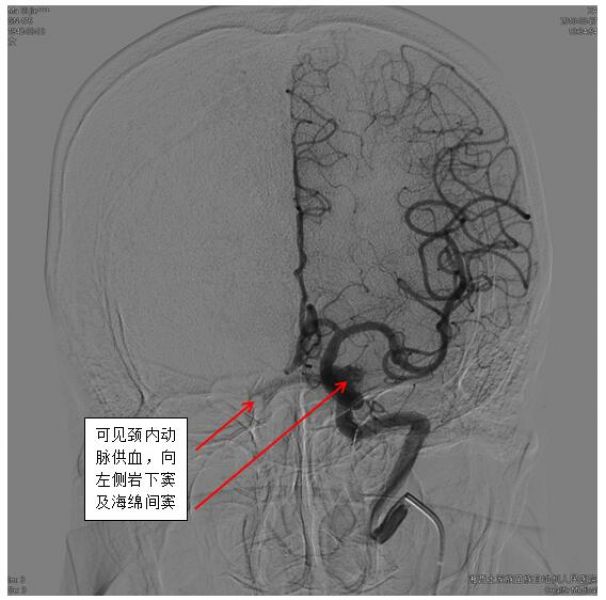

一旦怀疑DAVFs,神经内科一病区医生迅速和患者及家属沟通,及时完成脑血管造影,第一时间确诊患者为海绵窦区DAVFs(供血动脉为左侧颈内动脉海绵窦段,向左侧岩下窦及通过海绵间窦向对侧岩下窦引流)。